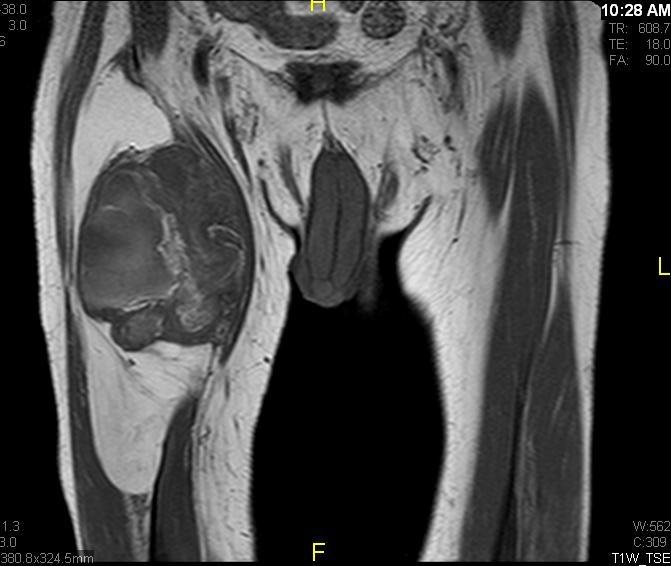

Fig. 7 & 8 Magnetic Resonance Image shows a large heterogeneous mass in the right thigh with low intensity signal on Axial (Fig. 7) and Coronal (Fig. 8) T1-weighted images admixed with high signal areas. The high signal areas represent low grade fatty tissue and low signal the dedifferentiated areas. Higher intensity signal is visible compatible with hemorrhage or necrotic tissue.

Fig. 9 Coronal fat suppressed T1-weigthed MR image demonstrates a large heterogeneous mass in the anterior compartment of the thigh with some areas suppressed corresponding with fatty areas within the tumor. Central hyper enhanced areas compatible with hemorrhage or necrosis.

Fig. 10 Axial T2 weighted MR image demonstrates a large well encapsulated heterogeneous mass with multiple thick internal trabeculations located in the anterior compartment of the thigh.